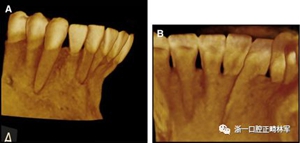

臨床檢查顯示固定保持器完好,弓絲沒有斷裂(圖13)。在下頜右側中切牙唇側和鄰近側切牙的舌側注意到有牙齦退縮。這些牙齒在退縮方向上存在顯著的扭矩差異。下頜的左側尖牙頰側錯位,而右側尖牙舌側傾斜。三維射線照片證實了下頜右側尖牙面?zhèn)妊啦酃菃适?,右側中切牙的喪失程度較輕。右側側切牙根也從舌側骨面上扭轉出來(圖14)。

圖14.三維立體圖像:A,面部和B,切牙根部的舌側,剛取出固定舌側保持器后。

再治療的目標是使牙齒恢復到冠和根的正常位置,并刺激退縮和牙根暴露區(qū)域新骨的形成。牙周手術和正畸聯(lián)合治療是完成這些所必需的。